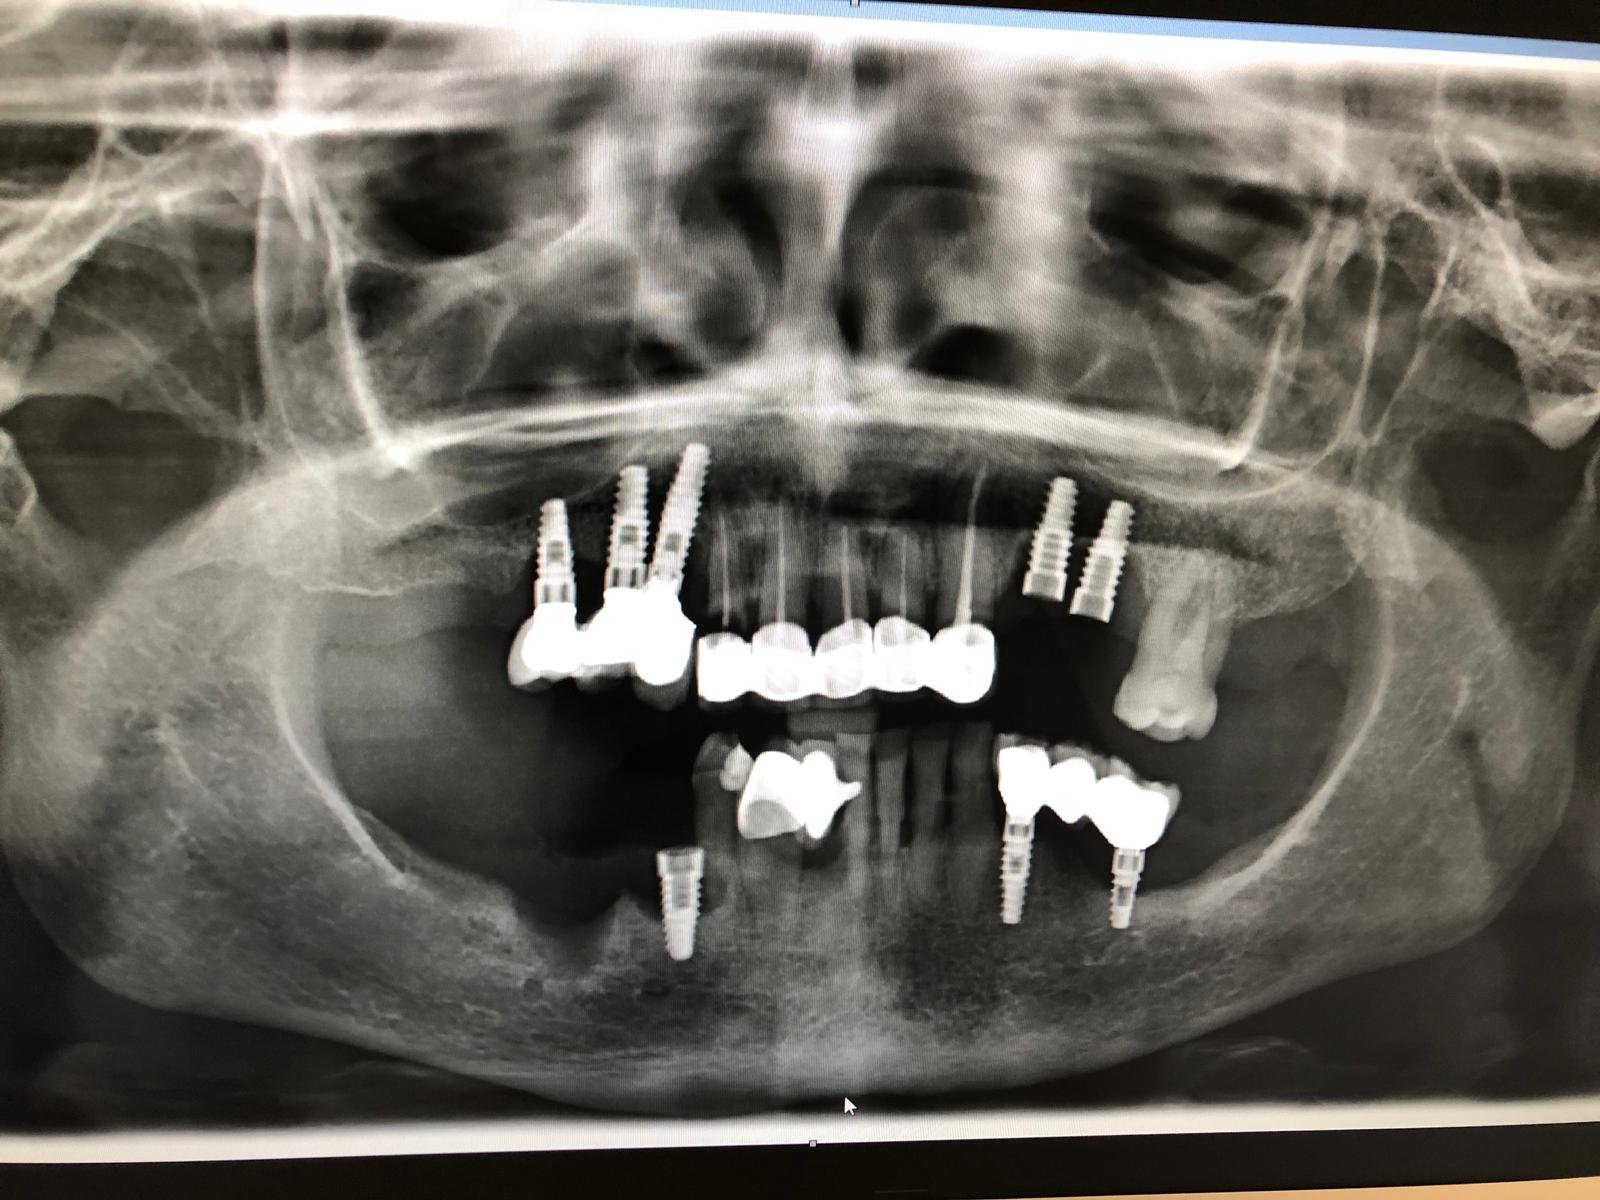

Paciente femenino llega a rehabilitación de sus implantes que fueron colocados en el pais Nicaragua C.A necesito saber qué tipo de implante y su marca para poder rehabilitarlos. Ella no [...]